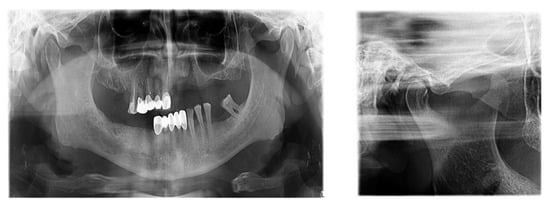

There is now good evidence that stress on the temporomandibular joints due to the absence of teeth in the posterior areas of the dental arches accentuates the signs and symptoms of dysfunction, but the causal link is not certain, in the sense that either dental occlusion causes the dysfunction or it results from the dysfunctional condition. The most recent evidence in the literature suggests that dental occlusion can be attributed to a secondary role in the onset of craniomandibular dysfunction, following trauma, oral parafunction, stress or dental iatrogenesis (Figure 5).

Figure 5.

TMJ tomography aspects in patients with periodontal injuries, open and shut position. (a) OPT with periodontal injuries; (b) TMJ aspect.

The study found statistically significant correlations between dental mobility and the degree of vertical resorption quantified on CBCT, with relevance to changes at the articular level and reflected by changes in shape or parameter changes during dynamic occlusion. It should also be noted that although the vertical lysis shows significant dimensions, the changes at the articular level captured on CBCT are not significant, which can be explained by the myocene influences at this level (Figure 7).

Figure 7.

Bone Changes in periodontal disease through CBCT. (a) Maxilla CBCT- Bone Changes in periodontal disease; (b) CBCT mandible- Bone Changes in periodontal disease.

Regarding the paraclinical grounds, several sections detected on the CBCT, offering horizontal and vertical selective images with precision, are quite significant. The combination of the two observed resorptions is the basis for the clinical modifications induced by dental mobility. Thus, 25% of the study group followed the specialized imaging evaluations by bringing TMJ tomographs in the paraclinical register and the CBCT of TMJ.